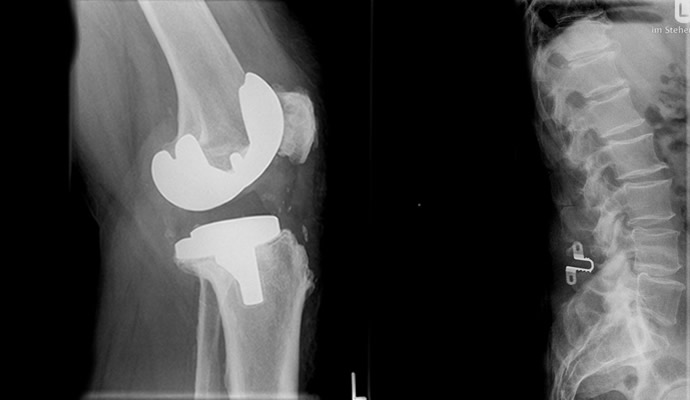

Von einer Strahlenquelle aus wird eine kurze Strahlung ausgesendet, die durch den Körper hindurch läuft, dabei abgeschwächt wird und auf einem Röntgenfilm zu einer Abbildung führt - dem Röntgenbild. Weiches Gewebe wie Haut, Muskeln und Fett absorbieren dabei wenig Strahlung, sie werden auf dem Film dunkel erscheinen. Hartes Gewebe wie Knochen hingegen absorbiert viel Strahlung, es erscheint als weiße Form. So können mithilfe der Röntgenstrahlen unterschiedliche Körperregionen und -gewebe dargestellt werden. Wichtige Röntgenuntersuchungen sind die Durchleuchtung, die Computertomografie sowie die Mammographie.

Seit Januar 2017 bieten wir Ganzbeinaufnahmen und Ganzwirbelsäulenaufnahmen zur exakten Evaluation von Beinlängendifferenzen, Beckenschiefstand, Fehlstellungen, Achsabweichungen und Skoliosediagnostik an. Diese Aufnahmen werden im Stehen angefertig und aus mehreren Einzelaufnahmen zusammengesetzt.